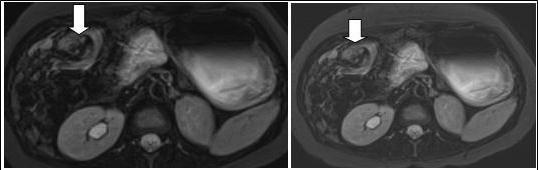

Figure 2A.Axial contrast-enhanced MRI scans show characteristic whirpool appearance of bowel and mesentery wrapping around superior mesenteric artery

Figure 2B.Axial contrast-enhanced MRI scans show characteristic whirpool appearance of bowel and mesentery wrapping around superior mesenteric artery

In that aspect, small bowel volvulus should always remain in the differential diagnosis in front of a pregnant woman presenting with abdominal pain during pregnancy, especially one like ours that was known for a previous surgery for appendicitis (a possible reason for the presence of the adhesions). Radiologic diagnosis of small bowel volvulus can be done by several technics. Plain abdominal film can be used, showing sometimes a typical pattern of dilated loops, but more often showing a normal radiological pattern due to a proximal position of the volvulus (with the loops being filled with liquid). Evidences on CT-scan are the presence of dilated bowel loops, intramural gas and the “whirlpool sign” (Cong et al, 2014; Shui et al, 2011)4, 12, but the use of technics exposing the foetus to radiations is debated. However, in their review, Cong et al 4emphasized the fact that those technics (and particularly plain radiography) are considered safe for the mother as well as for the foetus (Cong et al, 2014)4. MRI is also safe and extremely precise in the diagnosis of small bowel obstruction (Vassiliou et al, 2012)13, sometimes also showing the “whirlpool sign” (Kouki et al, 2013)7 and ultrasonography has been reported to be useful in some instances (Cong et al, 2014)4 but it can also remain completely negative. In our case, while cholangio-MRI suggested the diagnosis, final diagnosis was given by intestinal MRI, showing a possible role for this technic in some unusual cases, in which doubts about the diagnosis or about the state of different abdominal structures remain. However, in cases in which clinical symptoms, laboratory and more basic radiological (plain abdominal film of CT-scan) are highly suggestive of this pathology, exploratory surgery should be started at the earliest time possible.